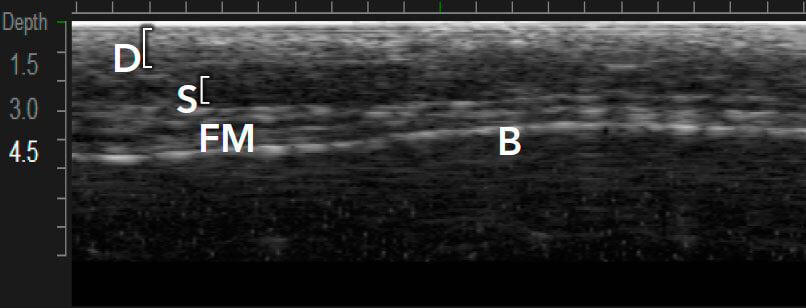

Ulthera – единственная технология с визуализацией в реальном времени

Примеры вариантов структуры кожи между индивидуальными пациентами1,12

Визуализация в реальном времени является основой Ultherapy®

Ultherapy® воздействует на ткани с помощью коллимированного звукового изображения. Затем доставляет микрофокусированный ультразвук с точной глубиной и температурой где лечение будет иметь наибольшее влияние.1,3

Визуализация в реальном времени необходима1,3,7:

MFU-V позволяет врачам точно видеть и учитывать все анатомические особенности в индивидуальном плане лечения, который будет являться эффективным.1